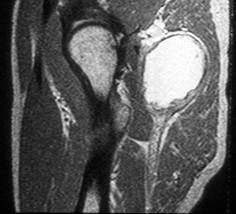

The proper diagnosis of nerve pain in hip starts with obtaining the health history of the patient. The doctor will also be asking questions about the onset of the pain and the triggers that worsen it; onset of fever; presence of diarrhea; and hurting in the abdomen or other joints. Physical examination will also be done. Then, imaging tests such as X-rays, CT scan, bone scan, and magnetic resonance imaging (MRI). Blood tests that include lymphocyte count, ESR (erythrocyte sedimentation rate) and CRP (C-reactive protein) are done to confirm nerve pain in hip.